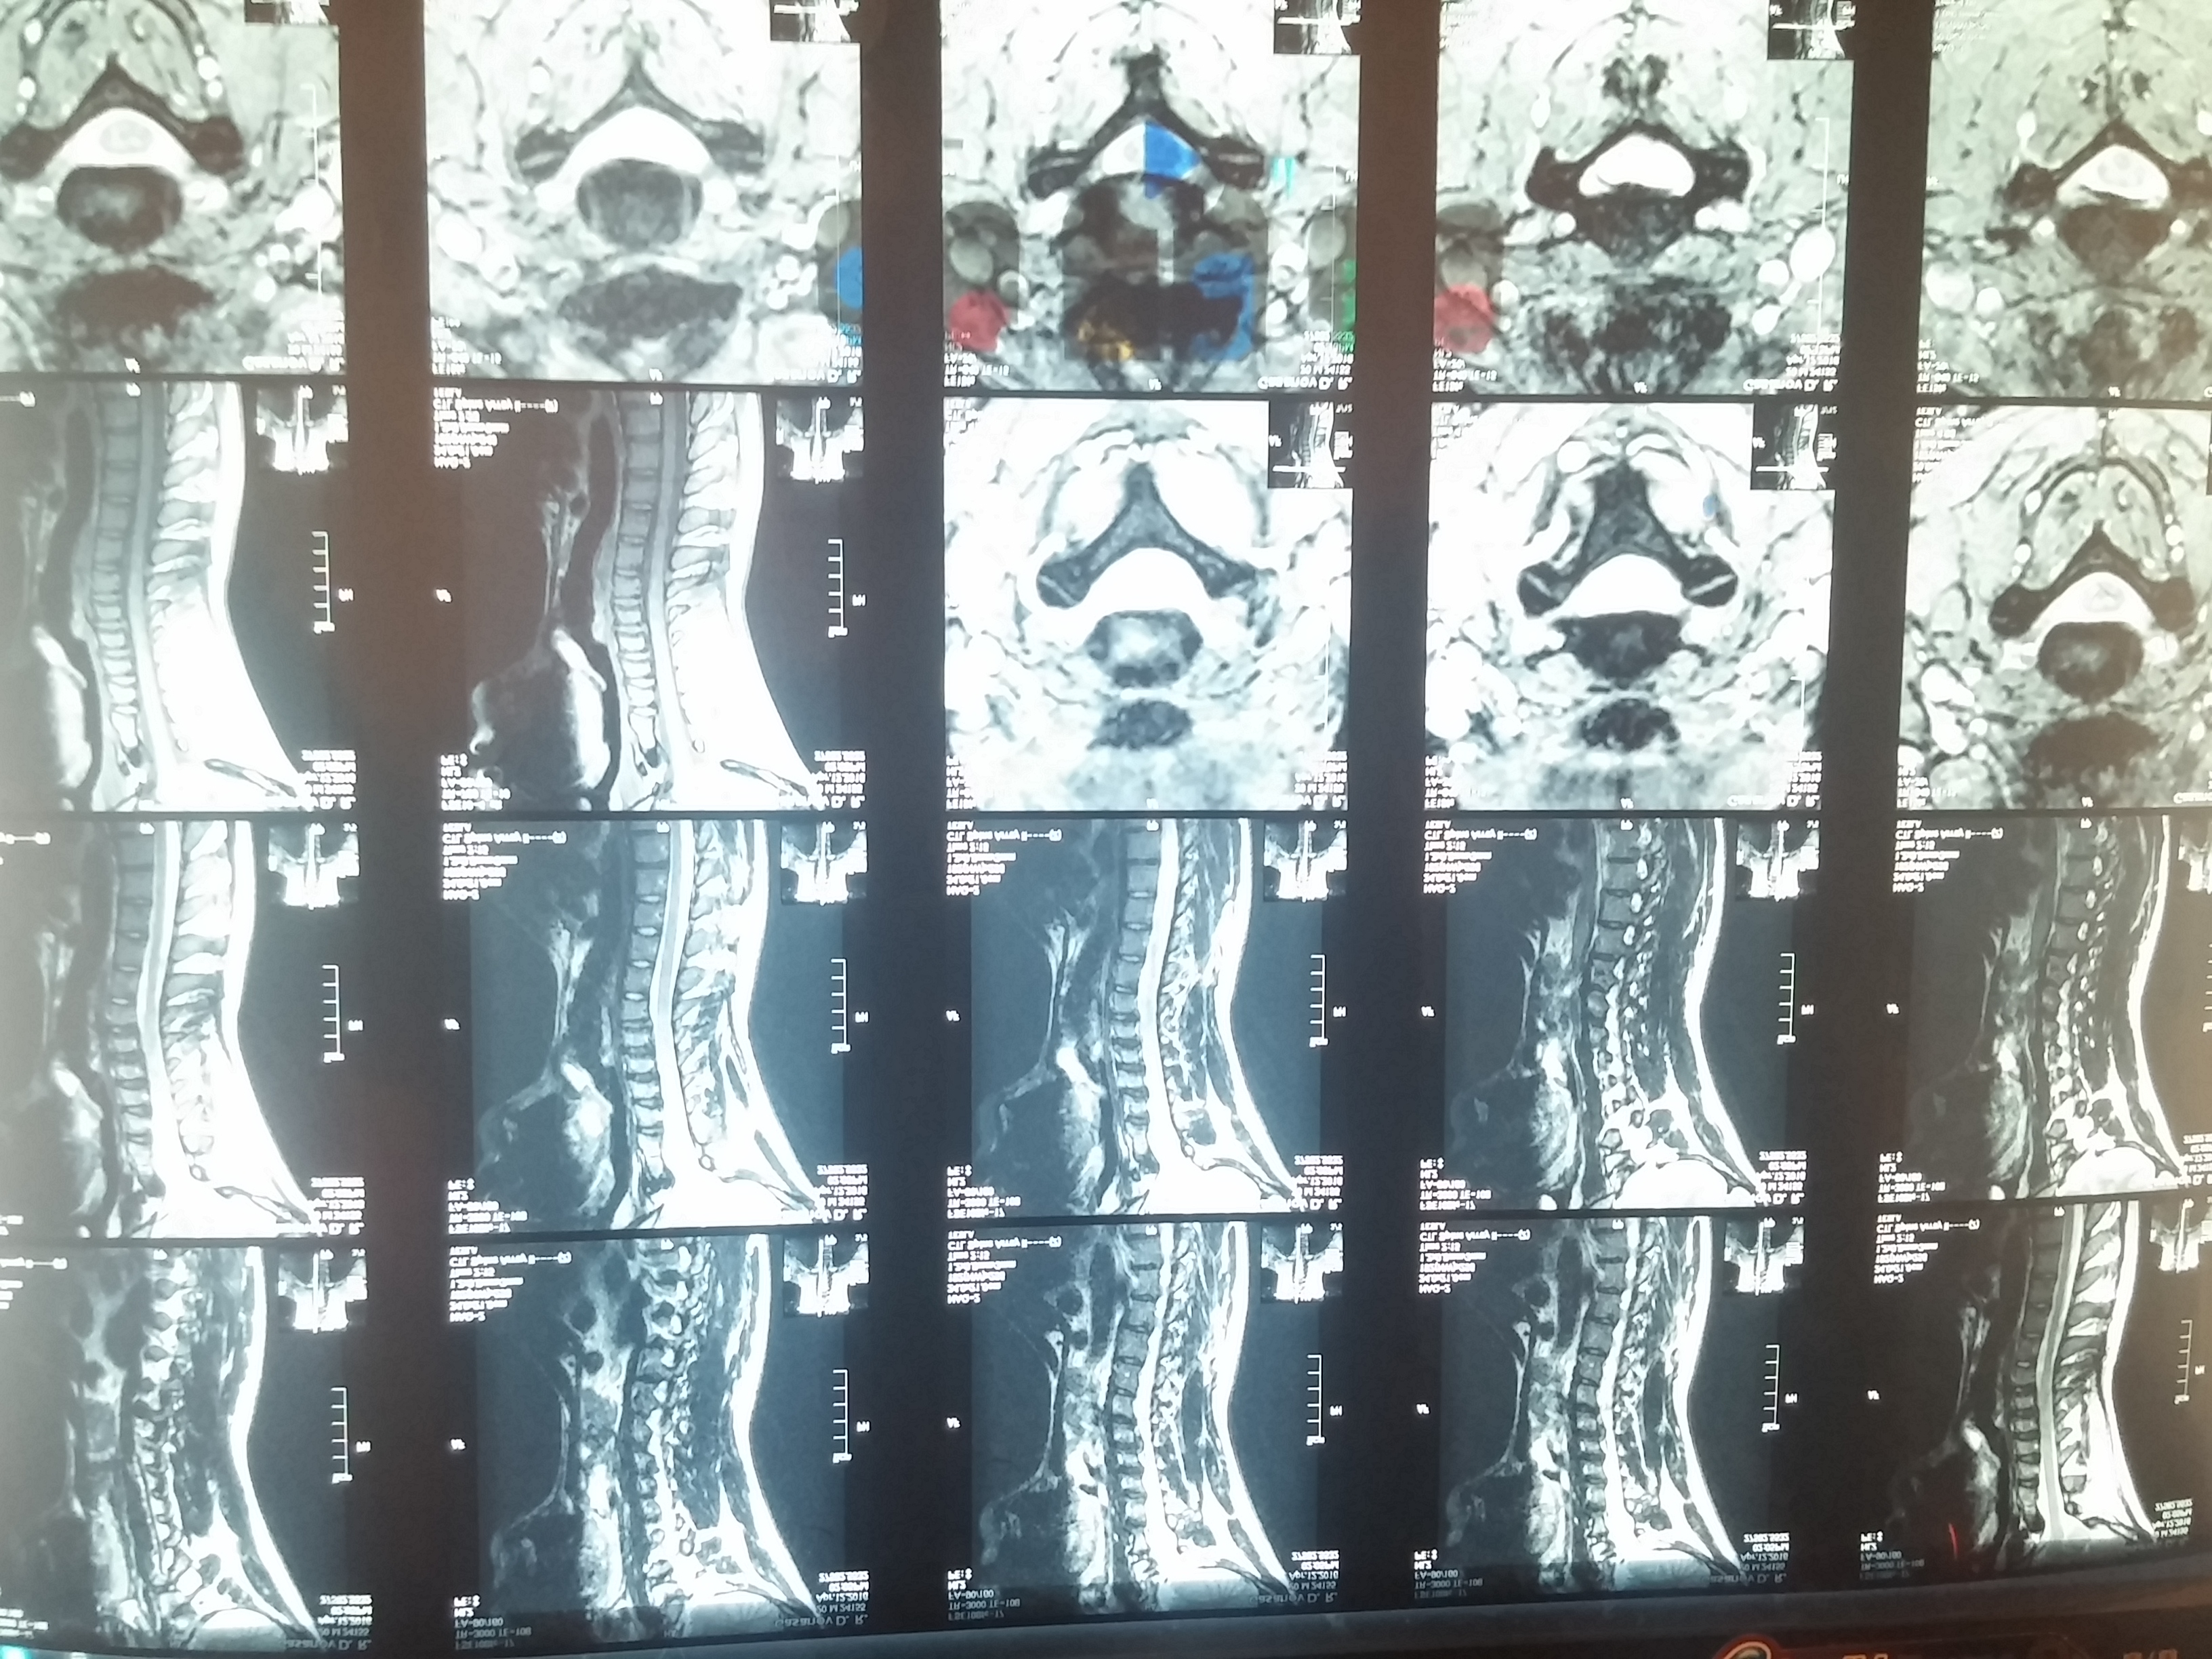

Здравствуйте,Посоветуйте, как дальше действовать, исходя из следующей картины МРТ.

На серии MP-томограмм шейного отдела позвоночника физиологический лордоз выпрямлен.

Гипогидратация и умеренное снижение высоты дисков С2-С7. Смежные замыкающие пластинки склерозированные, с ровными четкими контурами.

Циркулярные протрузии дисков СЗ-С4-С5 до 0,2 см.

Правосторонняя дорзально-Парамедианная грыжа диска С5-С6 до 0,4 см, высотой 0,7 см, на основе 1,2 см.

И Иеризка левосторонняя дорзально-Парамедианная грыжа диска С6-С7 до 0,25 см, на основе 0,7 см.

Гипертрофия и склероз задней продольной связки на уровне С4-С7 сегментов. Вторичный спинальный стеноз на уровне сегментов СЗ-С7 до 1,1; 0,9; 0,8 и 0,9 см соответственно.

Спинной мозг расположен в центре спинального канала. Участков его патологического расширения или сужения не обнаружено. Структура спинного мозга с гомогенной интенсивностью МР-сигнала.

Краниовертебрального переход без особенностей.

Патологических изменений в паравертебральных мягких тканях, на уровне исследования, не выявлено.

Вывод: дегенеративно-дистрофические изменения м / х дисков С2-С7 (дискоз).

И Циркулярные протрузии дисков СЗ-С4-С5, правосторонняя дорзально- Парамедианная грыжа диска С5-С6 и левосторонняя дорзально-Парамедианная грыжа диска С6-С7. с вторичным спинальным стенозированием.

Симптомы жгучая боль в правом плече и тянущая боль в правой руке,спазмы в области шее.